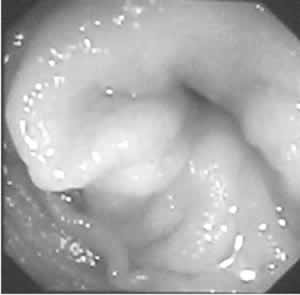

图2

狭窄表面黏膜充血糜烂,散在浅溃疡

腹部彩超:左肾动脉未显示,余腹腔动脉及分支未见异常。肾血流图:左肾灌注和功能极差。心电图示窦性心律,有广泛ST-T改变。超声心动图未见异常。经颅多普勒彩超(-),瞬目反射阴性。鼻窦X线片:左上颌窦炎。胸部高分辨CT(HRCT):右肺斜裂上方少许片状影,病变较外院CT明显吸收,胸水完全吸收,双肺间质纹理略厚。胃镜:慢性浅表性胃炎,病理:较多嗜酸粒细胞浸润。结肠镜:横结肠肝曲狭窄,表面黏膜充血,散在浅溃疡(图1,图2);病理示结肠黏膜慢性炎症,有多量嗜酸细胞浸润(图3)。右滑车上淋巴结活检为慢性淋巴结炎,有散在嗜酸细胞浸润。